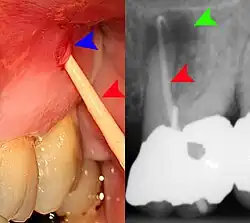

Clinical & xray correlation of pericoronitis

clinical shot of pericoronitis

An operculum (green arrow) over a partially erupted lower left third molar tooth. There is minimal inflammation and recurrent swelling.

xray of pericoronitis

A radiograph of the above tooth showing chronic pericoronitis, operculum (blue arrow) and bone destruction (red arrow) from chronic inflammation. Tooth is slightly disto-angular.

Pericoronitis is inflammation of the soft tissues surrounding the crown of a partially erupted tooth.[25] The lower wisdom tooth is the last tooth to erupt into the mouth, and is, therefore, more frequently impacted, or stuck, against the other teeth. This leaves the tooth partially erupted into the mouth, and there frequently is a flap of gum (an operculum), overlying the tooth. Bacteria and food debris accumulate beneath the operculum, which is an area that is difficult to keep clean because it is hidden and far back in the mouth. The opposing upper wisdom tooth also tends to have sharp cusps and over-erupt because it has no opposing tooth to bite into, and instead traumatizes the operculum further. Periodontitis and dental caries may develop on either the third or second molars, and chronic inflammation develops in the soft tissues. Chronic pericoronitis may not cause any pain, but an acute pericoronitis episode is often associated with pericoronal abscess formation. Typical signs and symptoms of a pericoronal abscess include severe, throbbing pain, which may radiate to adjacent areas in the head and neck,[21][26]: 122  redness, swelling and tenderness of the gum over the tooth.[27]: 220–222  There may be trismus (difficulty opening the mouth),[27]: 220–222  facial swelling, and rubor (flushing) of the cheek that overlies the angle of the jaw.[21][26]: 122  Persons typically develop pericoronitis in their late teens and early 20s,[28]: 6  as this is the age that the wisdom teeth are erupting. Treatment for acute conditions includes cleaning the area under the operculum with an antiseptic solution, painkillers, and antibiotics if indicated. After the acute episode has been controlled, the definitive treatment is usually by tooth extraction or, less commonly, the soft tissue is removed (operculectomy). If the tooth is kept, good oral hygiene is required to keep the area free of debris to prevent recurrence of the infection.[21]: 440–441